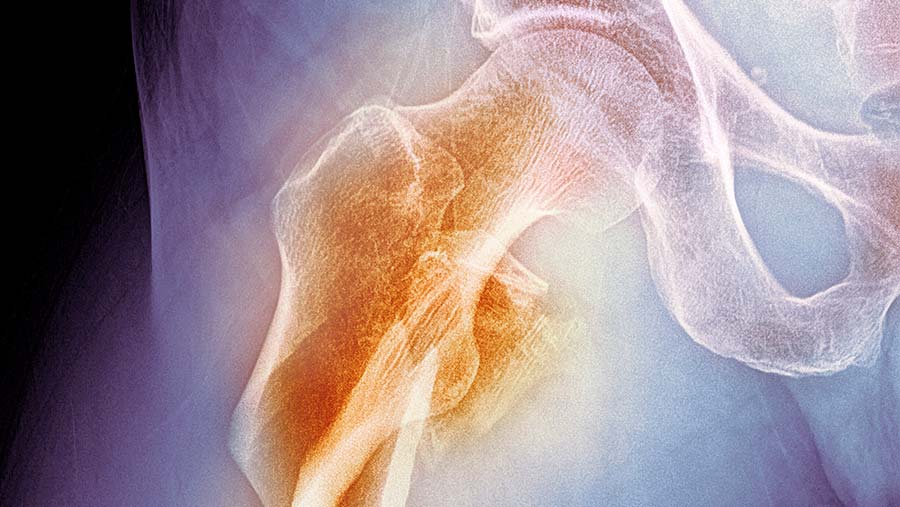

The results from an 18-year study reveal that vegans have a higher risk of fractures anywhere in the body compared with meateaters, while all non-meat eaters have a significantly greater risk of hip fractures.

“The biggest differences were for hip fractures, where the risk in vegans was 2.3 times higher than in people who ate meat.”